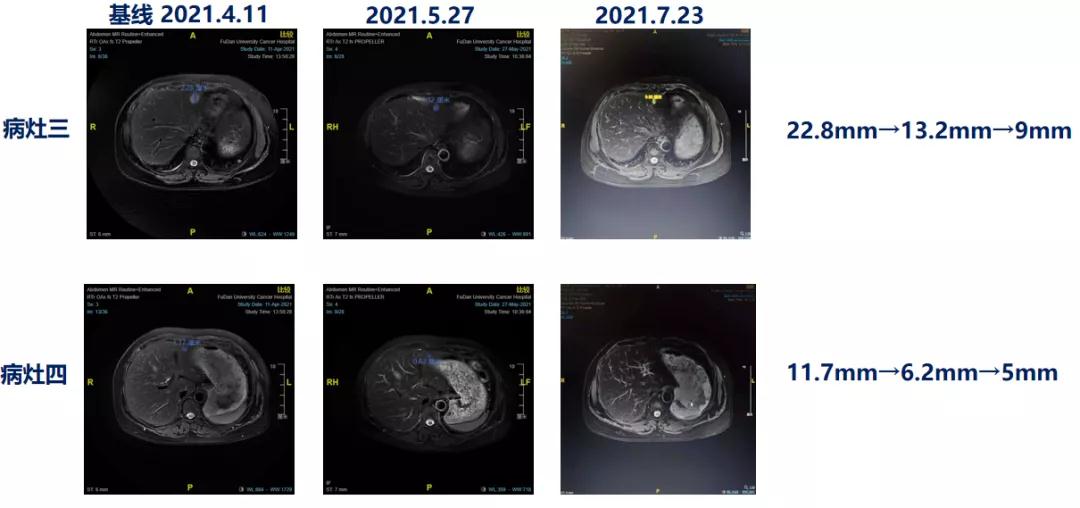

2021.04.11 肝脏、颅内病灶PD。

2021.04.20予优替德隆治疗至今。

用药5周期后:

靶病灶:肝脏(MR)9mm+5mm,脑(MR)15.1mm,肺(CT)6.8mm+6.8mm;靶病灶直径总和=42.7mm,达PR。

非靶病灶:non-CR/non-PD。

总体疗效评价:PR。

临床实践中,优替德隆在多线进展的患者中依然具有应用价值。通常来讲,患者经历多线治疗后很难有单药治疗的机会,但该病例中的患者6线经艾立布林治疗后,应用优替德隆进行7线治疗,目前患者获得PR,且不良反应为Ⅰ~Ⅱ级,耐受性良好。这也提示优替德隆与之前应用的抗微管类药物并不存在完全的交叉耐药,同时上述实践经验及试验证据也表明,优替德隆可为蒽环和紫杉治疗失败的晚期乳腺癌患者带来新的治疗希望,是多线治疗失败后患者的重要治疗选择。